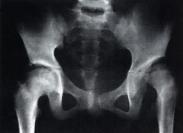

單純性髖關(guān)節(jié)前脫位(圖1),遠(yuǎn)遠(yuǎn)少見于后脫位,據(jù)布拉(Brav)統(tǒng)計(jì)為后脫位的14%,阿福克(Aufanc)等統(tǒng)計(jì)為后脫位的4%,沙摩波遜(Thompson)等統(tǒng)計(jì)為后脫位的9%。